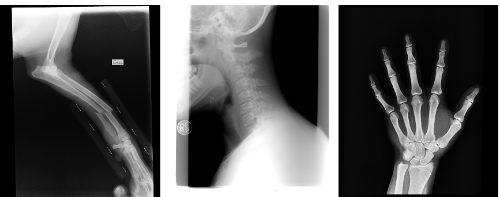

콘드로이친의 가장 잘 알려진 효능 중 하나는 관절 보호입니다. 콘드로이친은 연골의 주요 구성 요소 중 하나로, 연골 조직의 탄력성과 부드러움을 유지하는 데 중요한 역할을 합니다. 연골은 뼈와 뼈가 맞닿는 부위에서 쿠션 역할을 하여 충격을 흡수하고, 관절의 마모를 방지합니다. 나이가 들면서 연골이 손상되거나 마모될 수 있는데, 이때 콘드로이친이 연골을 재생시키고, 손상을 줄여주는 효과를 발휘합니다. 연구에 따르면, 콘드로이친은 퇴행성 관절염 환자들의 통증을 완화하고, 관절의 유연성을 개선하는 데 도움을 줄 수 있다고 합니다.

콘드로이친은 손상된 연골의 재생을 촉진하는 데도 효과적입니다. 연골 손상은 시간이 지나면서 악화될 수 있지만, 콘드로이친은 연골 세포의 성장을 촉진하여 손상된 부위를 복구하는 데 도움을 줍니다. 이는 특히 무릎 관절염이나 고관절염과 같은 질환을 가진 이들에게 중요합니다. 연구에 따르면, 콘드로이친을 섭취하면 연골 조직의 두께가 증가하고, 관절의 기능이 회복될 수 있다고 합니다. 따라서, 콘드로이친은 연골 손상 예방 및 치료에 중요한 역할을 할 수 있습니다.

또 다른 콘드로이친 효능은 골다공증 예방입니다. 골다공증은 뼈의 밀도가 감소하고, 뼈가 약해져 골절 위험이 증가하는 질환입니다. 콘드로이친은 뼈의 밀도를 유지하는 데 도움을 줄 수 있으며, 뼈의 건강을 증진시킵니다. 연구에 따르면, 콘드로이친은 뼈의 칼슘 흡수를 촉진하고, 뼈 조직의 강도를 증가시켜 골다공증 발생 위험을 낮출 수 있습니다. 따라서, 콘드로이친을 섭취하면 나이가 들면서 발생할 수 있는 골다공증을 예방하는 데 기여할 수 있습니다.